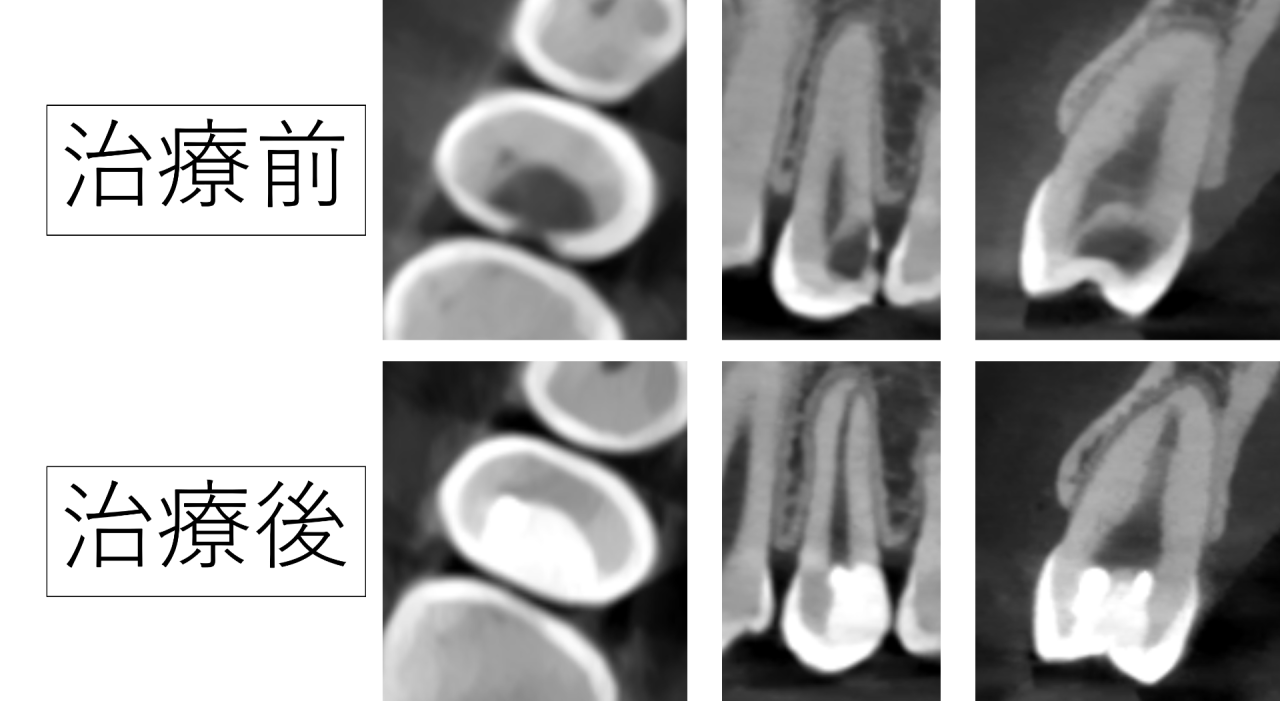

レントゲン(CT)を撮影したところ、虫歯が歯の内部の深い部分まで進んでいて、神経にほとんど接しているところまで大きくなっている様子が確認できます。

実際に治療してみるとレントゲンよりも虫歯は深く進んでいる事があるため、通常の虫歯治療では神経は残せないだろうと予想しました。